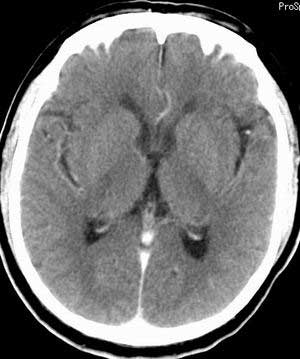

脑实质密度均匀,未见异常密度灶,脑沟裂池室形态大小正常,中线结构居中.

双侧乳突蜂房密度呈气体样,慢性乳突炎可能性不大,

双侧颞叶脑实质密度均匀未见异常密度灶,

考虑颅内未见异常。